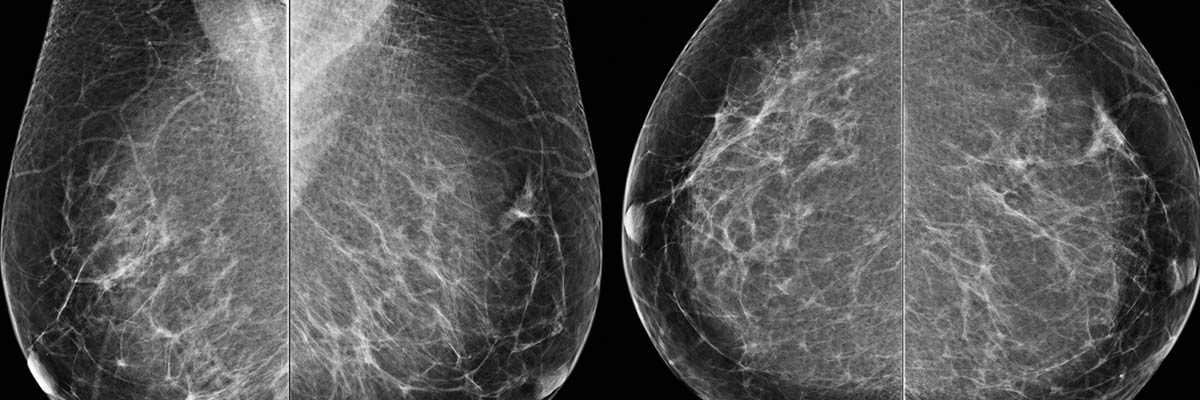

Mammography

At DRCTC, our digital mammography system produces high- quality images that allow for better visualization of breast tissue, aiding in the early detection of breast cancer. Early detection has been shown to dramatically increase the survival rates of women afflicted with this deadly disease.

The Siemens is a state-of-the-art breast cancer detection system designed to improve the quality and comfort of mammograms. This advanced system offers physicians precise viewing options that were never possible with conventional film.

A physician can zoom in, magnify and optimize different parts of the breast tissue, enhancing readability and interpretation of the images. Plus, the images can be sent anywhere in the world to be viewed by another physician.

Compared to conventional film, digital images give better visibility of the breast, particularly near the skin line and chest wall. They�re ideal for women with implants. For women with dense breast tissue, digital is far superior and may involve less radiation than a standard mammography.

In addition, digital exams usually take less than half the time of traditional exams and result in a 20 to 30 percent reduction in callbacks.